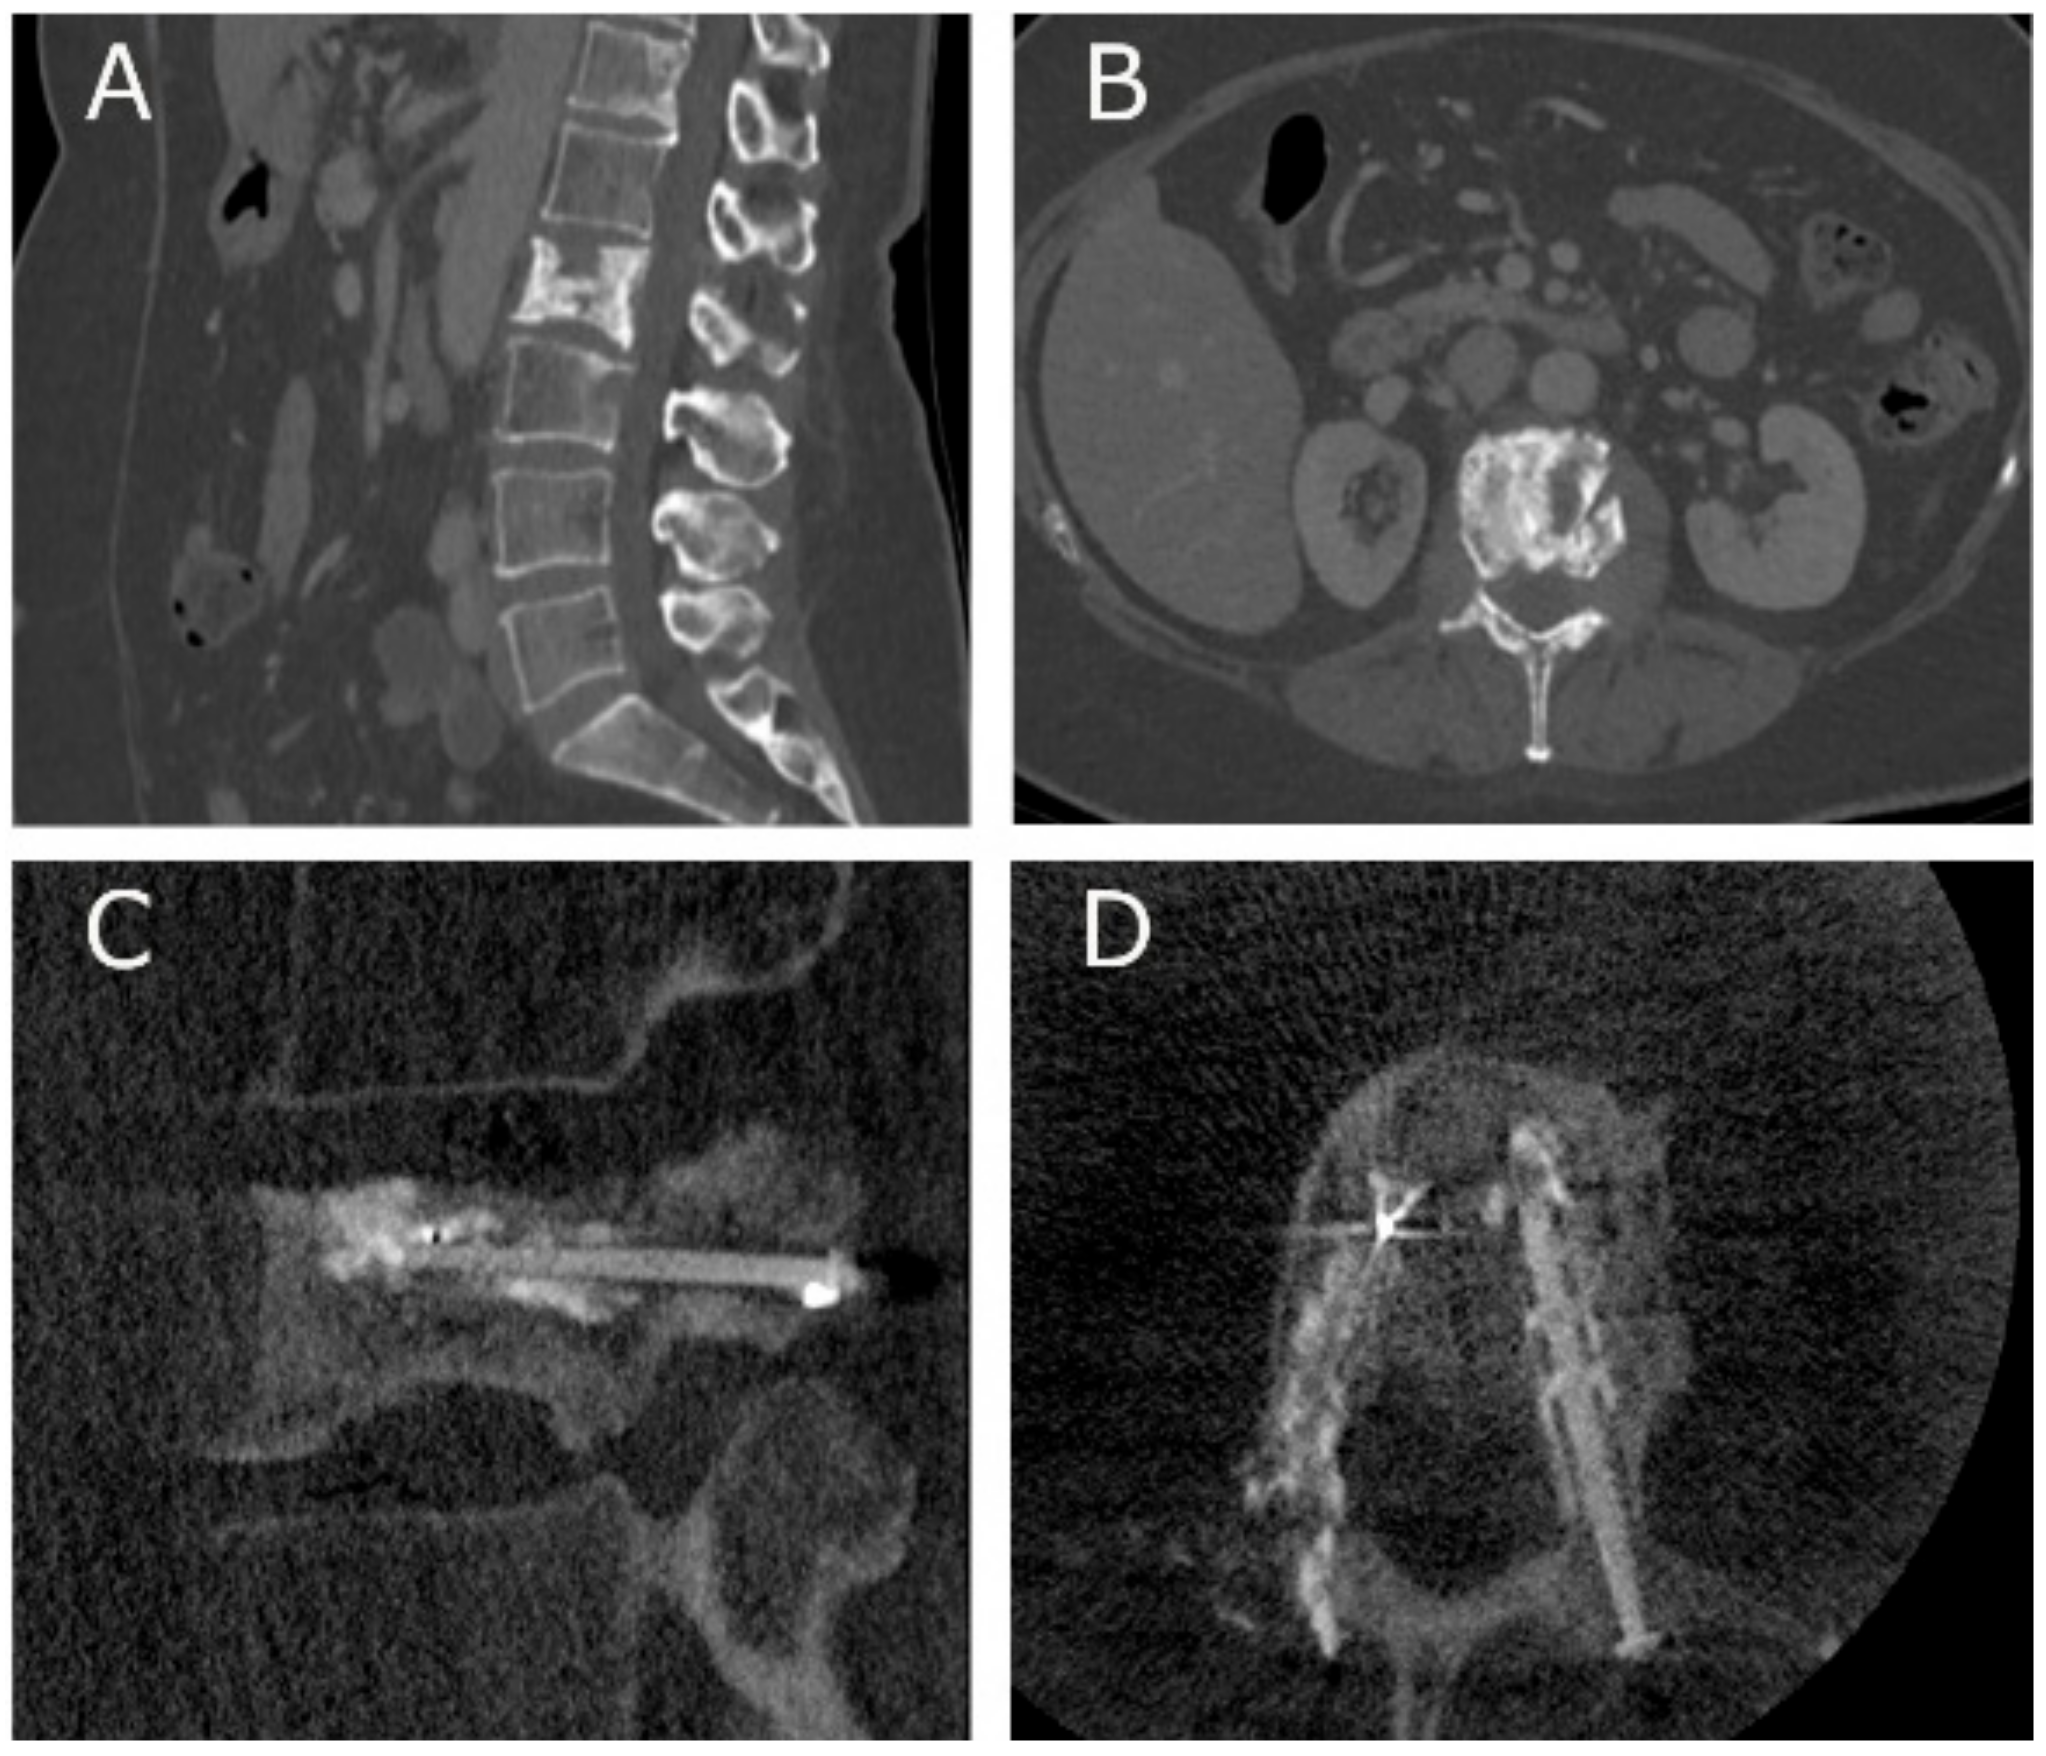

- Cianfoni, A.; Distefano, D.; Pravatà, E.; Espeli, V.; Pesce, G.; Mordasini, P.; La Barbera, L.; Scarone, P.; Bonaldi, G. Vertebral body stent augmentation to reconstruct the anterior column in neoplastic extreme osteolysis. J. NeuroInterv. Surg. 2018, 11, 313–318. [Google Scholar] [CrossRef]

- Cornelis, F.H.; Petitpierre, F.; Fabre, T.; Gille, O.; Amoretti, N.; Hauger, O. Percutaneous low-pressure bone stenting to control cement deposition in extensive lytic lesions. Eur. Radiol. 2017, 27, 3942–3946. [Google Scholar] [CrossRef]